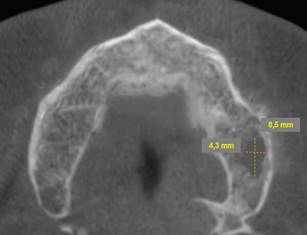

Periapical radiographs were initially ordered. They showed a loss of continuity of the bony trabeculae with irregular, faint osteolytic areas without root debris or foreign bodies (Fig.4 A, B). A CBCT of the maxilla was ordered to evaluate the extent of the lesion. The CBCT showed a radiolucent and osteolytic area at the maxillary bone tissue, measuring 8.5 mm x 5.4 mm, with irregular, poorly defined borders, and which did not involve the buccal, palatine, or maxillary sinus cortical areas (Fig. 5). Microscopic study of the necrotic tissue debris confirmed areas of bone tissue necrosis with inflammatory infiltrate, confirming the MRONJ diagnosis.

Cross-section showing an osteolytic area on the left side of the maxilla measuring 8.5 mm x 4.3 mm is observed.